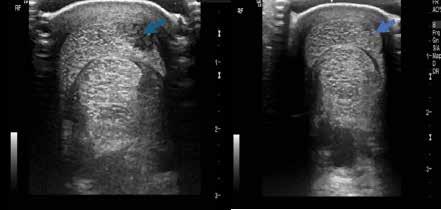

This is an ultrasound image of an injury of the superficial digital flexor tendon before and

after regenerative medicine and therapeutic exercise. Recheck imaging shows the degree that the tendon injury has healed and allows your veterinarian to advise you to continue to advance your horses exercise.